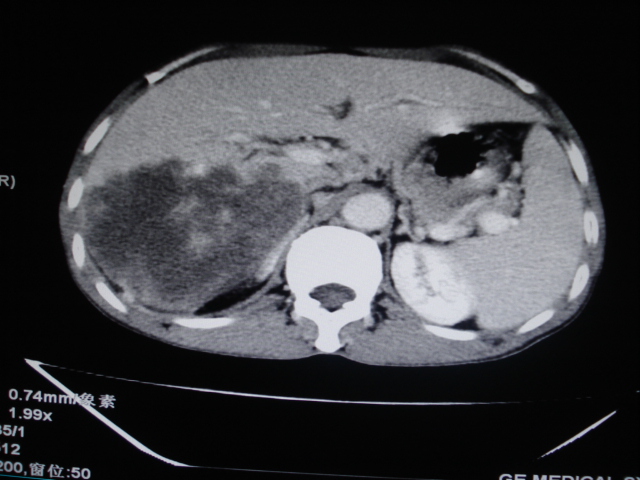

男性,62岁。肝右叶占位,平扫及增强如下,延迟期为15分钟扫描。

给病史及实验室检查!多考虑胆管细胞癌;右肾囊肿。

1)不均匀性脂肪肝。2)肝硬化。3)肝右叶肝癌不排除。4)右肾囊肿。

延迟期怎么进去了   血管瘤?

血管肉瘤可能。